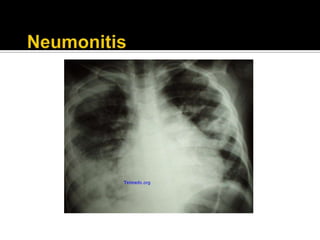

 Compromiso pulmonar

 Dolor articular Quejas generales  cansancio, astenia  Lesiones en la piel  Diagnósticos renales  Artritis  Síndrome de Raynaud  Quejas diversas del sistema nervioso central  Cambios a nivel de mucosa  Quejas gastrointestinales  Inflamación pleural  Enfermedad de los ganglios linfáticos  Inflamación del pericardio  Compromiso pulmonar  Inflamación muscular  Inflamación del músculo del corazón  Pancreatitis